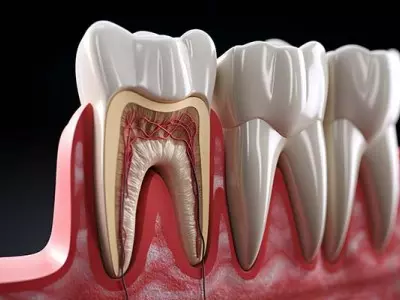

W tym wydaniu m.in: zatrzymane jedynki stałe, leczenie stomatologiczne dzieci w znieczuleniu ogólnym finansowanym przez NFZ, leczenie zapalenia przyzębia metodą niechirurgiczną, relacja drobnoustroje – przyzębie.